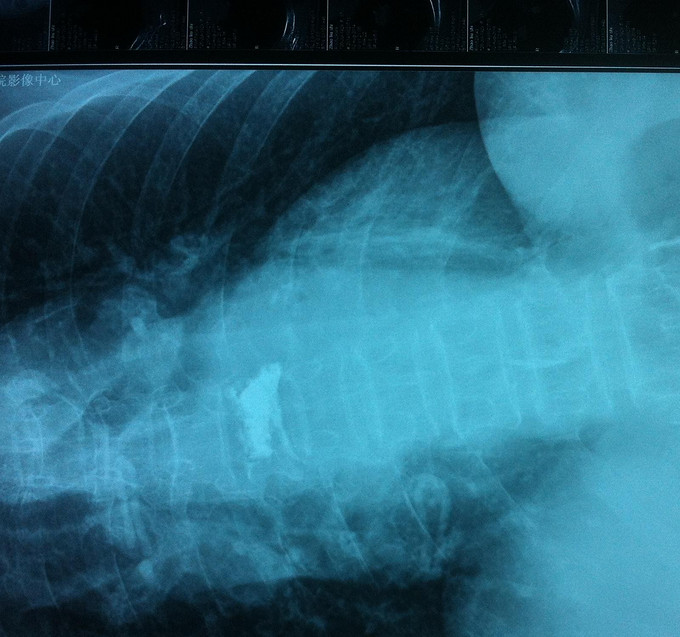

专科查体:背部后凸畸形,背部叩痛,腰骶部无叩痛,双下肢感觉无减退,双下肢肌力4-5级,双侧膝腱反射++,巴氏征阴性。影像学检查:X-Ray;骨质疏松、胸8楔形变。MR:胸8压缩性骨折,新鲜。